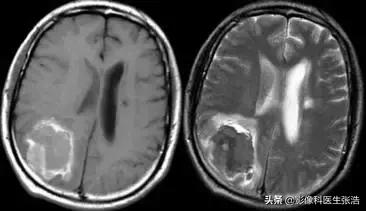

(2)急性期:一般为1-3天。

该期红细胞内为去氧血红蛋白,它有4个不成对电子,具有顺磁性,局部场强不均,T1加权像仍成稍低信号。

脑出血急性期